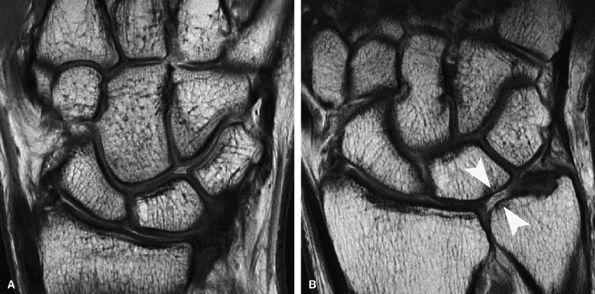

FIGURE 7.20 ● (A) Coronal fast spin-echo MR image of the wrist in a 28-year-old patient with normal articular cartilage. (B) A 61-year-old patient with ulnolunate impaction syndrome demonstrates full-thickness cartilage loss over the distal ulna and proximal pole of the lunate (arrowheads), with sclerotic change in the subchondral bone. Note also the full-thickness central defect in the articular disc.